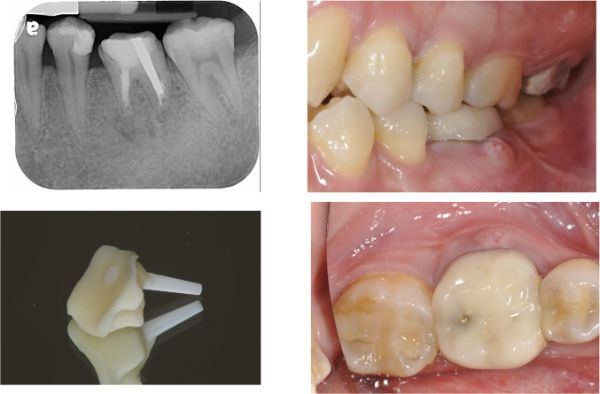

螺絲固位全鋯冠

固位後口內照

術後X光

術前、術後比較